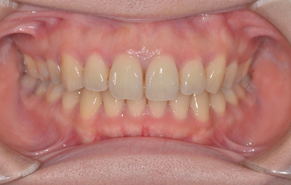

前歯のガタガタと口元の突出感を改善したいと言われました。

口元の突出感の改善には抜歯が必要となり、上下左右の計4本を抜歯しています。治療後は抜歯した隙間を使って配列して、閉じることで口元を入れました。

リスク

1.歯根吸収:ありませんでした

2.虫歯:右下の親知らずによる影響で右下第2大臼歯の虫歯を確認。その後処置を行いました。

3.前歯の叢生改善に伴う歯間鼓形空隙(歯肉の退縮)が起こりうる。若干の退縮はあったものの、肉眼的に確認できる大きさではなくその後徐々に回復。

4.後戻り:後戻り:保定装置の協力とフォローをしっかり行います。